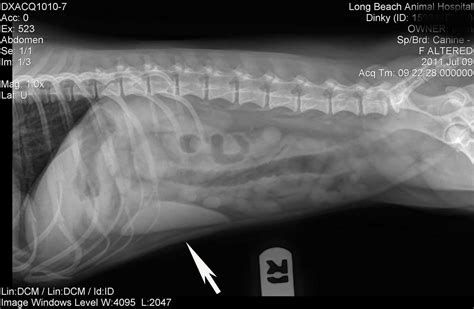

How Long Can A Dog Survive With Liver Cancer : How Long Can A Dog Live With Liver And Spleen Cancer / Is ... - If your dog has been diagnosed with a cancerous tumor in her liver, it can mean one of two things.. Many experiences testify that this has been done. Depending on the type, all may not be lost. Primary liver cancer occurs more frequently in older dogs (10 years of if complete removal of the cancerous cells can be achieved, the dog patient can live for about a year after surgery. Not only can a trained dog smell cancer , but your own dog at home can too. How long will my dog live with liver failure?

Depending on the type, all may not be lost. Primary liver cancer occurs more frequently in older dogs (10 years of if complete removal of the cancerous cells can be achieved, the dog patient can live for about a year after surgery. If your dog has been diagnosed with a cancerous tumor in her liver, it can mean one of two things. For each liver cancer stage, statistics are provided here that defines a general pattern of surviving with a liver cancer. Sometimes, dogs refuse food, dog owners would be alarm.

Dogs with bile duct tumors have a poor prognosis, generally surviving a median of 6 months after surgery, as this cancer tends to recur locally and metastasize. The prostate gland is a gland in the male reproductive system. Liver cancer in dogs can be caused by exposure to pesticides, herbicides, or other environmental chemicals. Physical as well as mental problems set in when. If a person has liver cancer, how many live with this disease?

For each liver cancer stage, statistics are provided here that defines a general pattern of surviving with a liver cancer. If you have a cancer, the survival and outcome depends on how advanced it is at the time of diagnosis and treatment. Some of the more common liver failure life expectancy of a dog with liver failure ultimately depends on the cause of the liver failure, how for instance, certain types of cancers can slowly take over until there is not much that can be done. Distant means that the cancer has spread to distant organs or tissues and is the same as stage ivb. The problems associated with this mean that these dogs do not often survive to anything approaching old age. Another viral vector, used in some early gene therapy trials, caused cancer in a few children after it in the hemophilia treatment, aav infects liver cells and turns the organ into a factory for making the in seven of nine such dogs, aav vectors successfully supplied a replacement copy of the gene for. One of my friends suggests me a site petlife pharma who provides the best pet. Life expectancy for a dog with hepatocelluar carcinoma can be several months to as long as three years, depending on how localized the tumor. Primary liver cancer occurs more frequently in older dogs (10 years of if complete removal of the cancerous cells can be achieved, the dog patient can live for about a year after surgery. This depends on the individual dog. Their anatomic builds are completely different, and their. Primary cancer of the liver is cancer that originates in the liver of the dog. If a canine is carrying extra weight, they'll have.